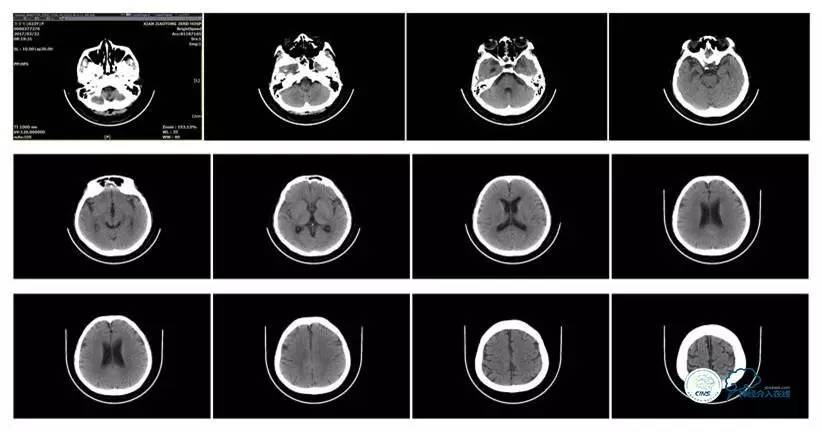

头颅CT

MRI T1

MRI T2

MRV